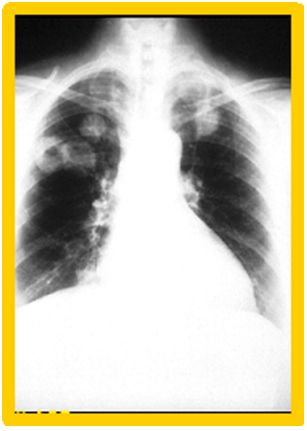

6. 一位68歲的男性患者最近半年來發現三次流鼻血,經耳鼻喉科醫師診斷為鼻竇炎及口鼻部黏膜潰瘍。因最近一個月久咳不癒且有血痰出現,X光檢查發現肺部有數個腫瘤陰影(如圖)。抽血檢查發現Hb 9.7 g/dl ,ANA 1:80 speckled,c-ANCA 33.6 IU/ml (normal <8 IU/ml),p-ANCA 1.4 IU/ml。VATS檢查並作病理切片發現並非惡性腫瘤。請問最有可能的診斷為下列何者? (A) Polyarteritis nodosa (B) Wegener's granulomatosis (C) Churg-Strauss syndrome (D) Microscopic polyangiitis (E) Behcet's disease